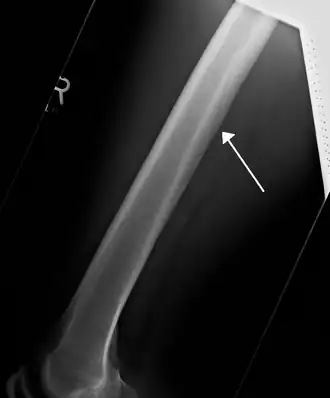

![]() Radiografía mostrando una arteria nutricia irrigando el fémur. | ||

Se conoce como arteria nutricia (TA: arteria nutriens) a cualquier arteria que irriga la médula ósea de un hueso largo.[1]

- Las arterias nutricias del fémur (arteriae nutriciae femoris). Se originan en la tercera arteria perforante. No presentan ramas.